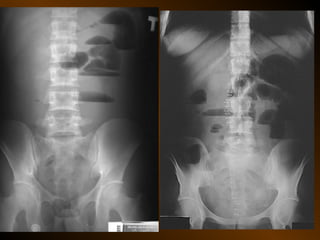

• HÌNH BỤNG KHÔNG SỬA SOẠN

• Kỹ thuật :

• Bao nhiêu phim ?

• Yếu tố kỹ thuật ?

• Tư thế nào quan trọng ?

• Cách phân tích

• 4 loại bất thường

• Chỉ định : hơi tự do

tắc ruột

sỏi niệu

Phân tích hệ thống:

- Khí tự do trong phúc mạc

- Khí trong ống tiêu hóa: hình thái

- Đánh giá thành ruột

- Tụ khí ngoài phúc mạc?

- Khí trong các cấu trúc ống khác

- Hình ảnh các cấu trúc mô mềm sinh lý

- Tụ dịch trong phúc mạc

- Các bóng mờ bệnh lý

- Các đóng vôi bệnh lý

- Khung xương, đáy phổi